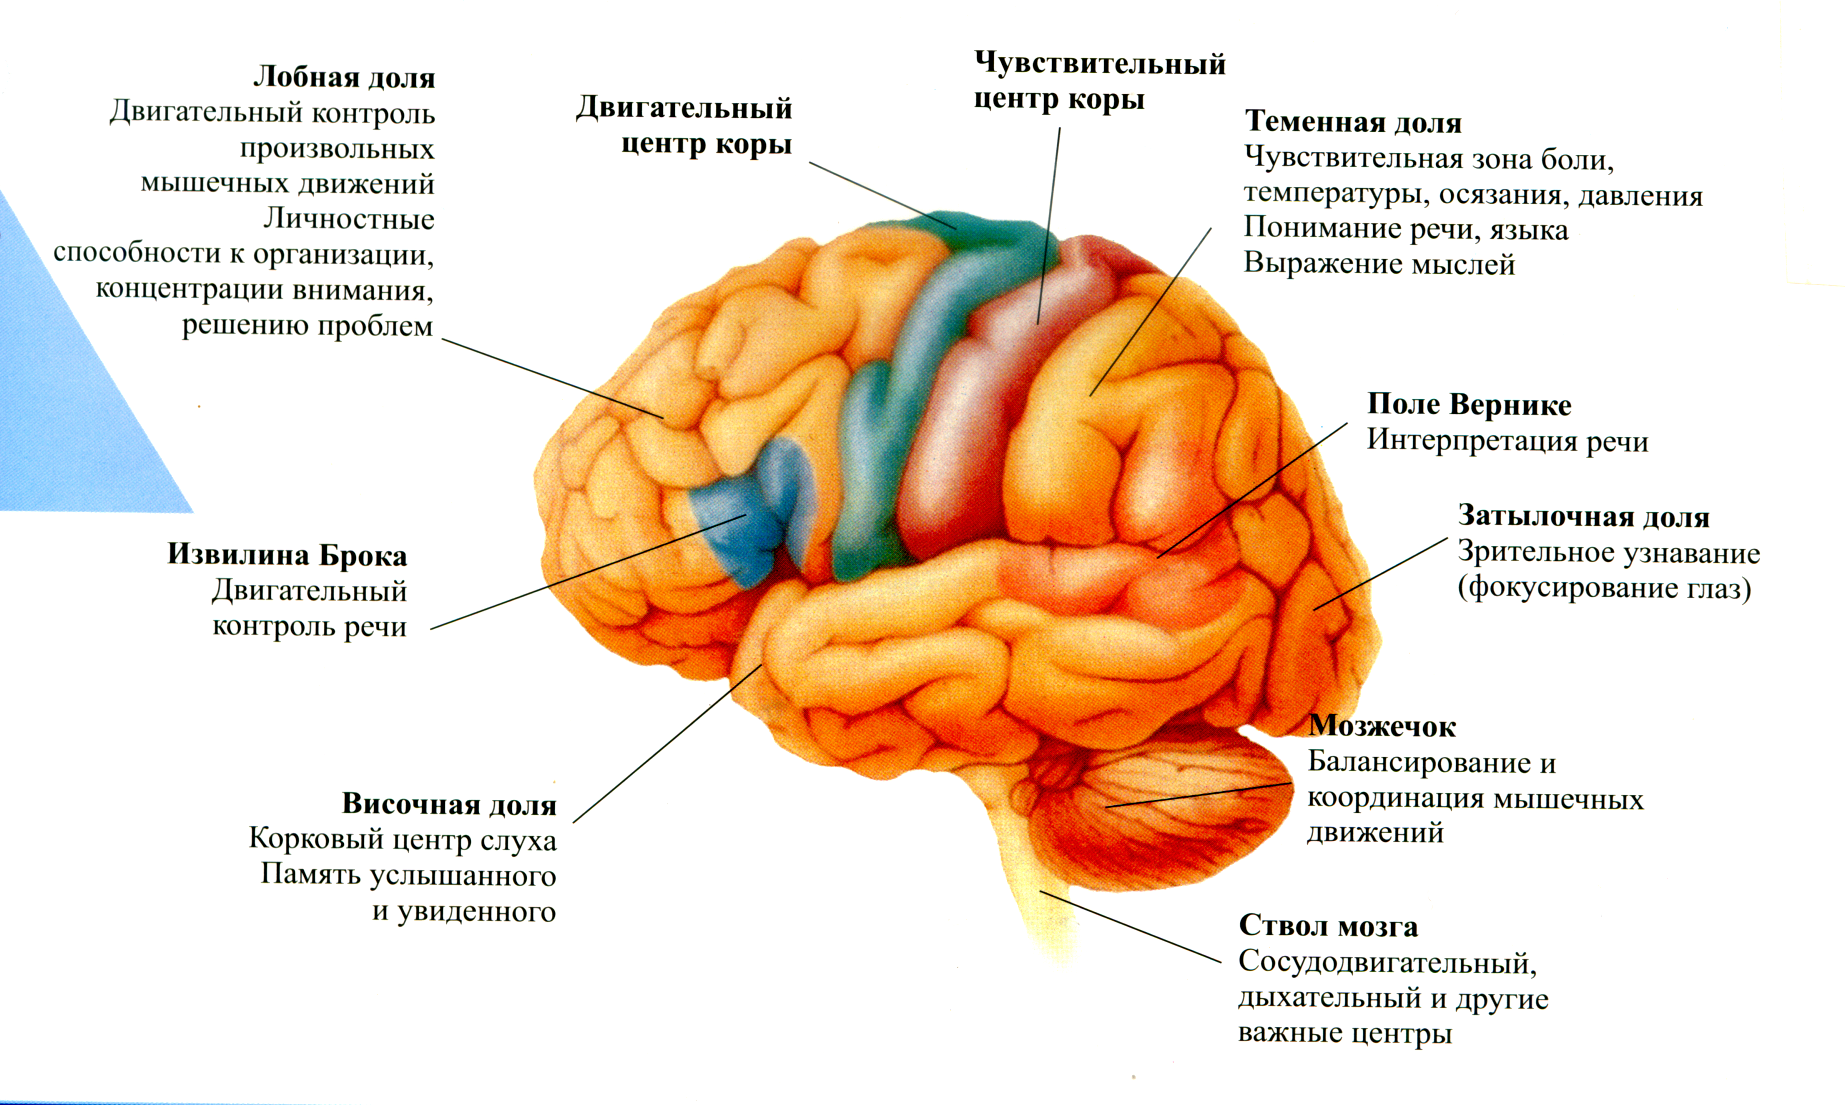

Анатомические снимки верхнелатеральной поверхности головного мозга